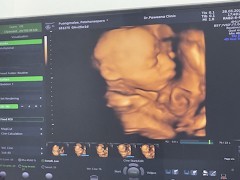

ภาพซาวด์4มิติ

ขอดูภาพซาวด์4มิติ ของแม่ๆท่านอื่นหน่อยคะ บ้านนี้ซาวด์ปัยน้องยิ้มเล่นไปด้วย ให้ทายว่าน้องเปนผญ.หรือผช.😊

ซาวด์ตอน28w น้องเป็นผู้หญิงงง😍😍

ซาวตอน25วีคคะ ผู้ชายคะ ☺️